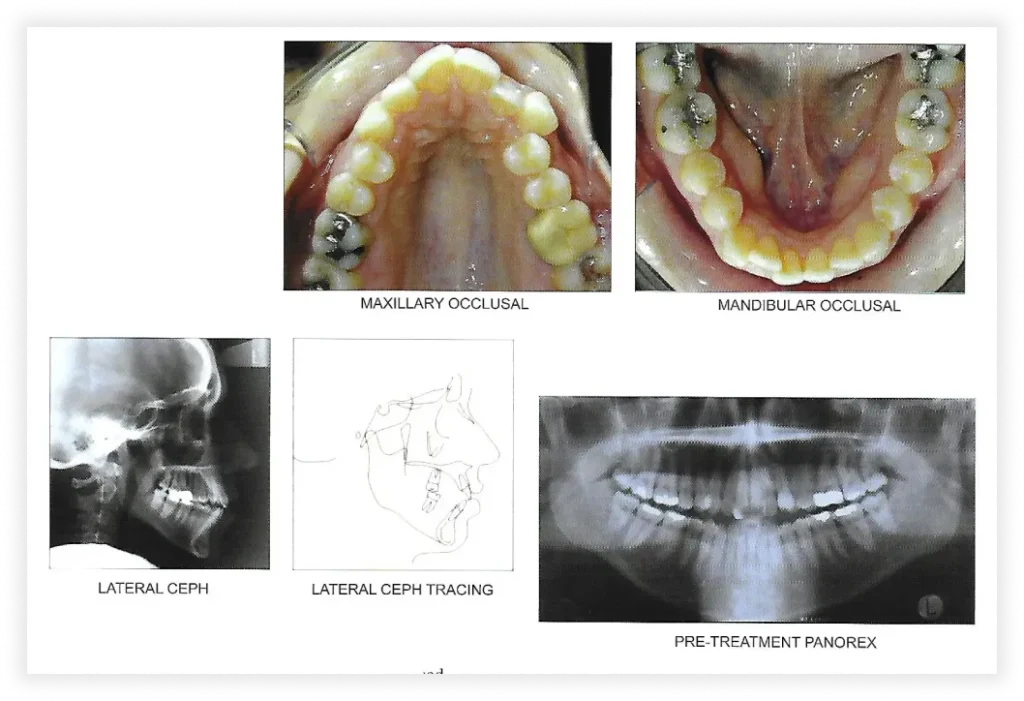

Case #3

Initial Photos

Final Photos